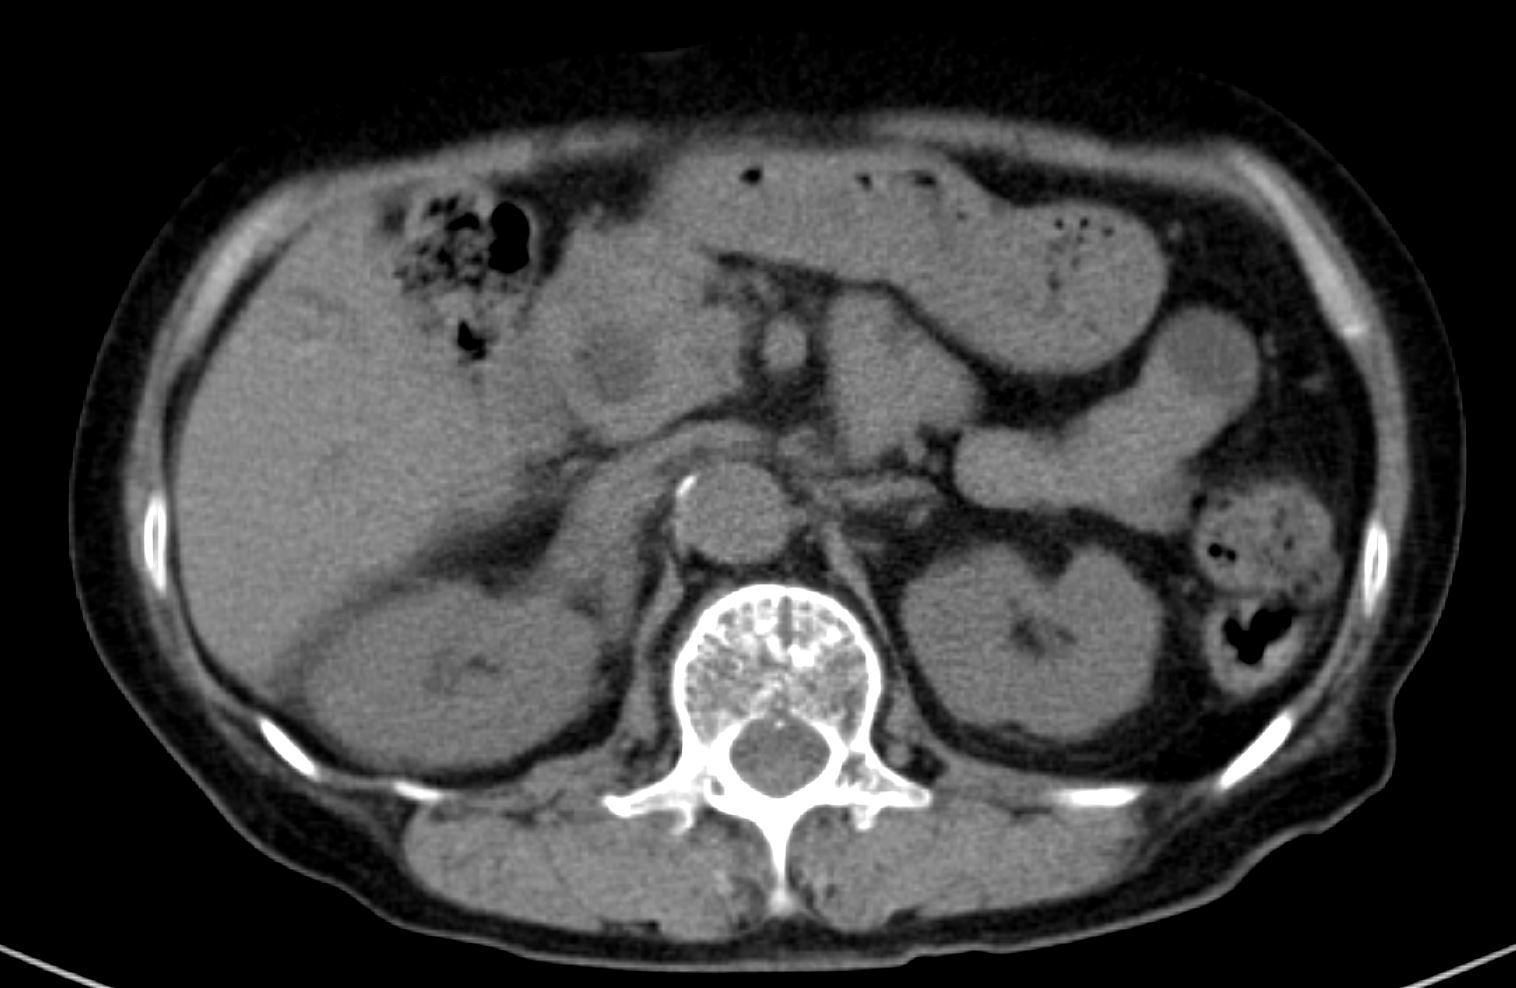

곧바로 촬영한 CT에서 여러개의 간내담관결석 및 전반적인 간내담관 및 간외담관 확장소견이 보입니다. 담관의 중심부 확장이 주변부 확장보다 더 심한 전형적인 proportional dilatation을 보입니다.총수담관(common bile duct)의 확장도 뚜렷하게 보이지만, 총수담관을 막고 있는 담관내 결석이나 국소병변 소견은 보이지 않습니다.

환자는 임상적으로나 임상검사 상 황달을 보이지 않았으며, CT 영상에서 간내담관결석 외에 담관의 확장을 일으킬 수 있는 병변은 확인되지 않았지만, 담관의 proportional dilatation은 장기간 총수담관을 막고 담즙의 배출을 방해하는 병변의 가능성을 암시합니다. 따라서 담관의 추가적인 확인을 위해 다음날 오전 초음파영상을 시행했습니다.